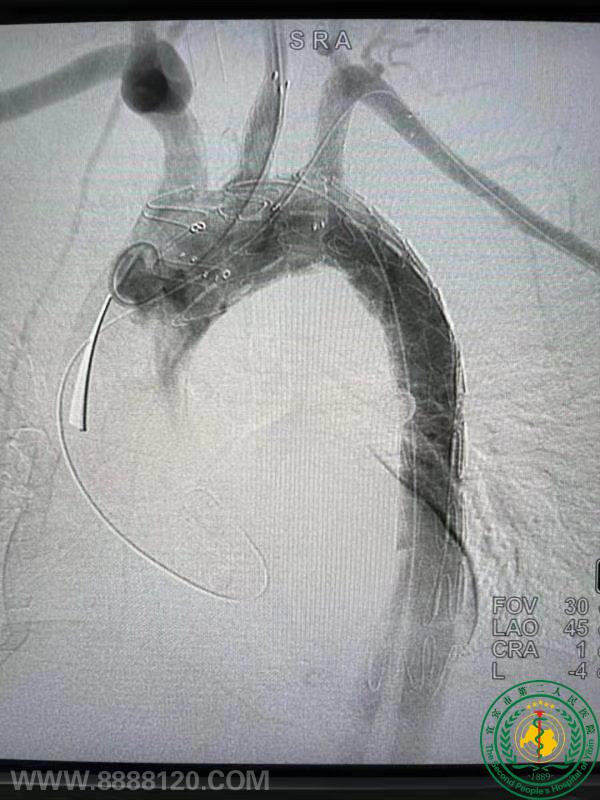

“大”手术 “小”操作 ---医院血管外科独立完成一场全腔内复杂主动脉夹层手术

“大”手术  “小”操作     ---医院血管外科独立完成一场全腔内复杂主动脉夹层手术32975